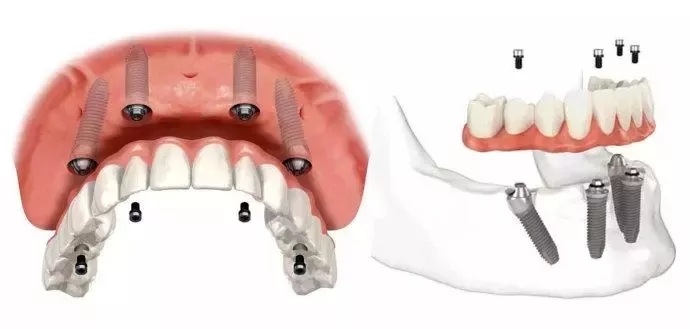

“半/全口微创即刻种植”采用的即为“桥墩式”种植修复,植入8颗种植体,即可恢复全口牙齿,而恢复半口牙齿则只需种入4颗种植体:2颗前牙部位的种植体垂直植入牙槽骨内,2颗中远部位的种植体采取倾斜角度种入牙槽骨内,然后在种植体的基台上安装“拱形连桥”牙冠,完成口腔种植修复。

All-on-4种植牙运用微创种植牙技术,无需植骨,在前牙部位牙槽骨垂直植入2颗种植体,远中部位通过倾斜方式植入2颗种植体,增大骨骼与种植体接触面,降低对垂直骨移植的需求,完全无视牙槽骨萎缩情况。通过此种方式完成种植修复后,24小时内即可戴上临时牙,戴牙后2小时便可恢复患者咀嚼功能,无需传统种植的漫长等待,适用范围更广,存活率高达98%以上,一次种植至少可保40年。

All-on-4结合倾斜植体和即刻负重等外科与修复方面的创新, 实现在手术当日即刻负重,只需4个植体就可做半口固定义齿修复。